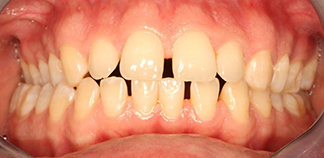

До лечения

Жалобы на неровные зубы.

Как лечили

Проведено ортодонтическое лечение на брекетах. Расширен верхний зубной ряд, убран перекрестный прикус, создано место для импланта.

Лечащий врач

МАРЦИ Анастасия Викторовна